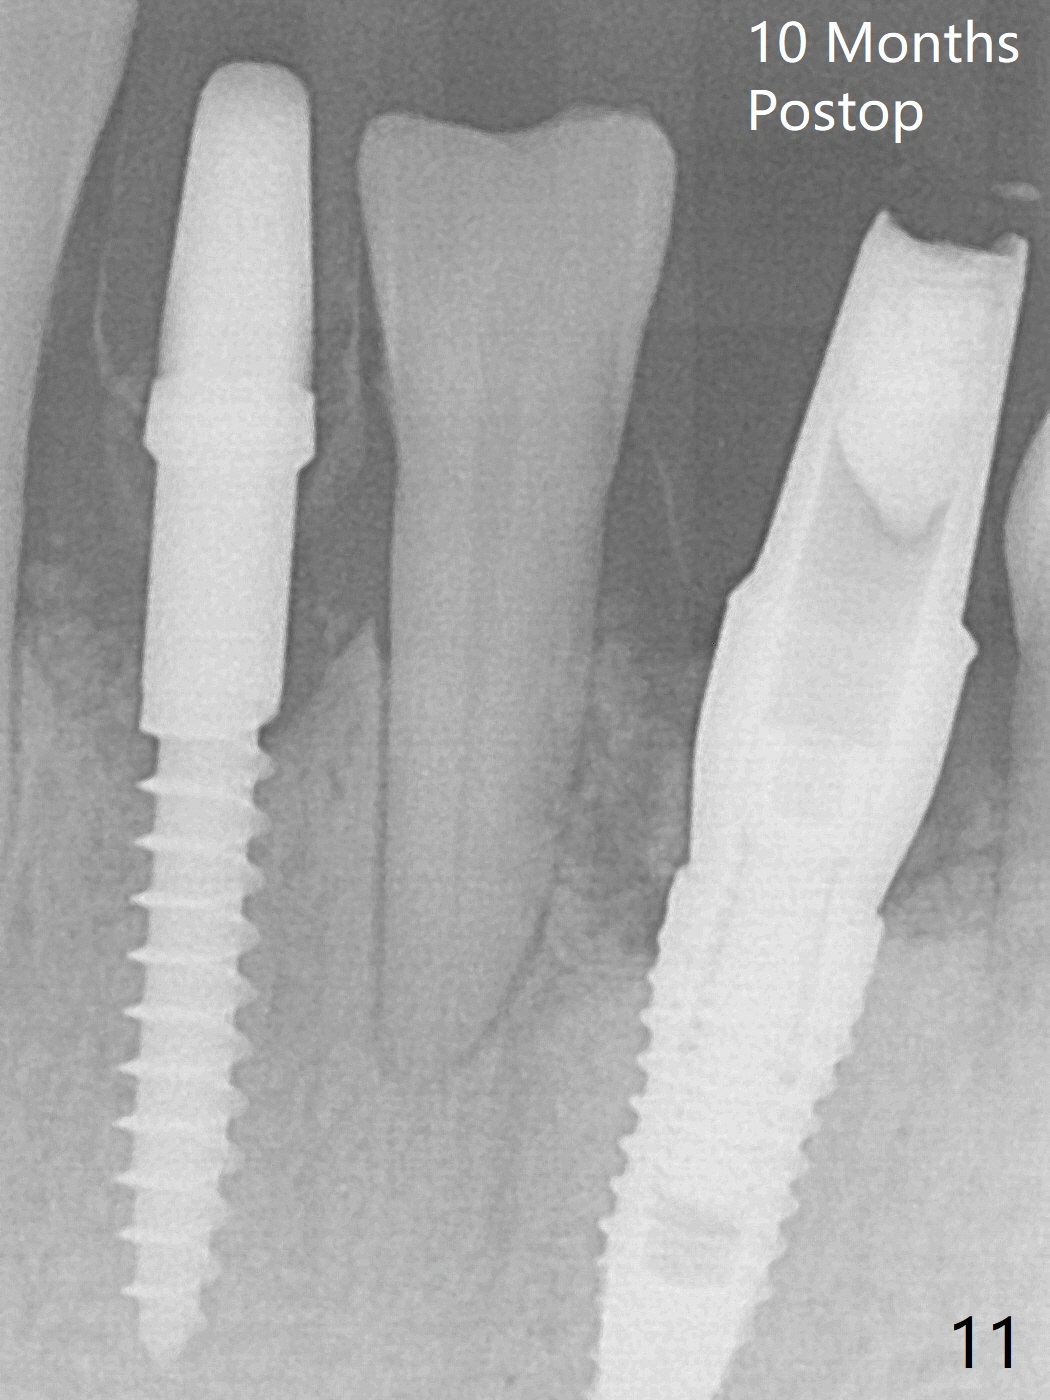

There is gingival inflammation at #25 buccally (Fig.1) and lingually (Fig.2). The bone loss is severe (Fig.3). Soft and hard tissue heights are 5 mm (cuff will be 4 mm) and 10 mm (implant will be 12 mm with 2 mm outside the native bone, Fig.4). The apex of the affected tooth appears deviated distal (Fig.5 *). The initial osteotomy happens to follow the long axis of the socket (Fig.6); to establish a correct trajectory, a new osteotomy should be made at the site labeled as a red line. In fact it is executed as planned (Fig.7). Because of the narrow flat ridge buccolingually, a 2.5x12(4) mm 1-piece implant is placed with >40 Ncm (Fig.8). With deeper placement of the implant, Vanilla graft is placed in 2 steps (Fig.9,10). The patient will return 2.5 months for extraction and implant of the fused teeth #22 and 23. No implant threads are exposed 10 months postop (Fig.11). CT taken 11 months postop shows that the 2.5 mm implant is in the middle of the bone (Fig.12) or 2 years post cementation (Fig.13).